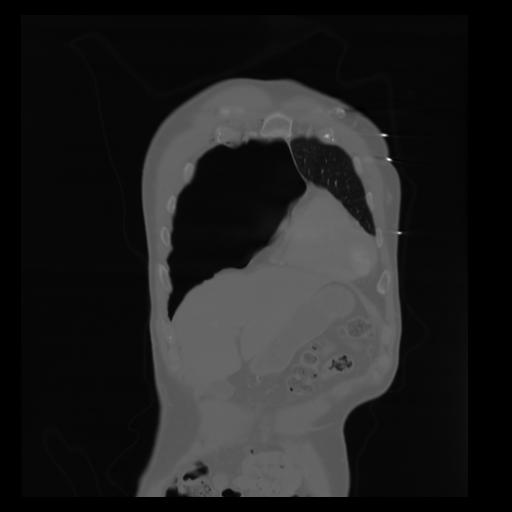

29 CUERPO,CE,Coronal,3.000,CUERPO,Coronal,